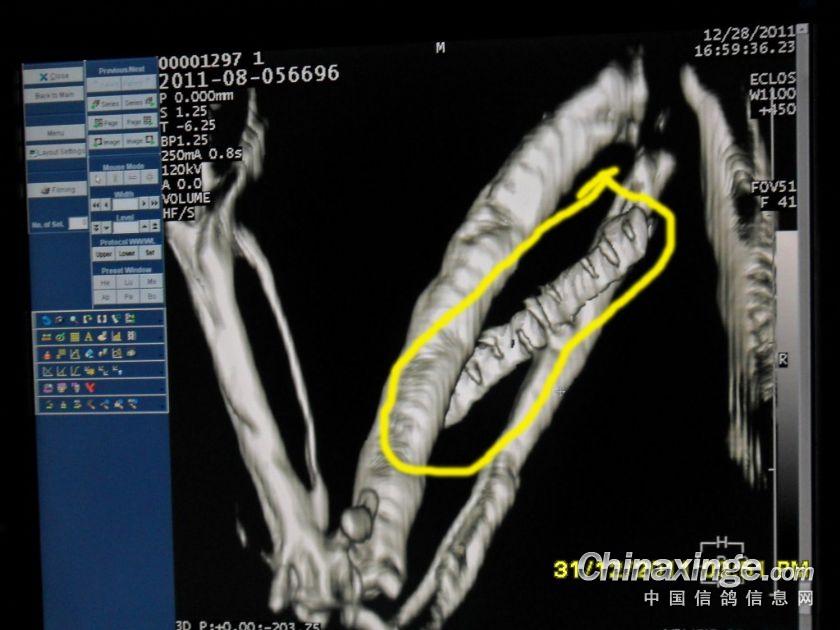

钢针插在翅膀内,翅膀肿胀,开笼后被迫落下!!!

金属物

在翅膀内的金属已经发炎

不同角度的金属物图片

用眼睛看谁能看出翅膀内有钢针!!!